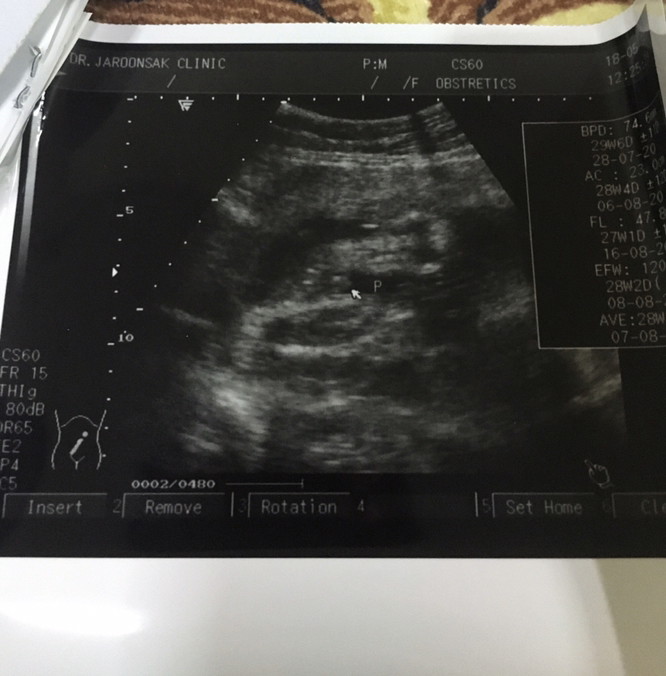

ตอน 6w 3d